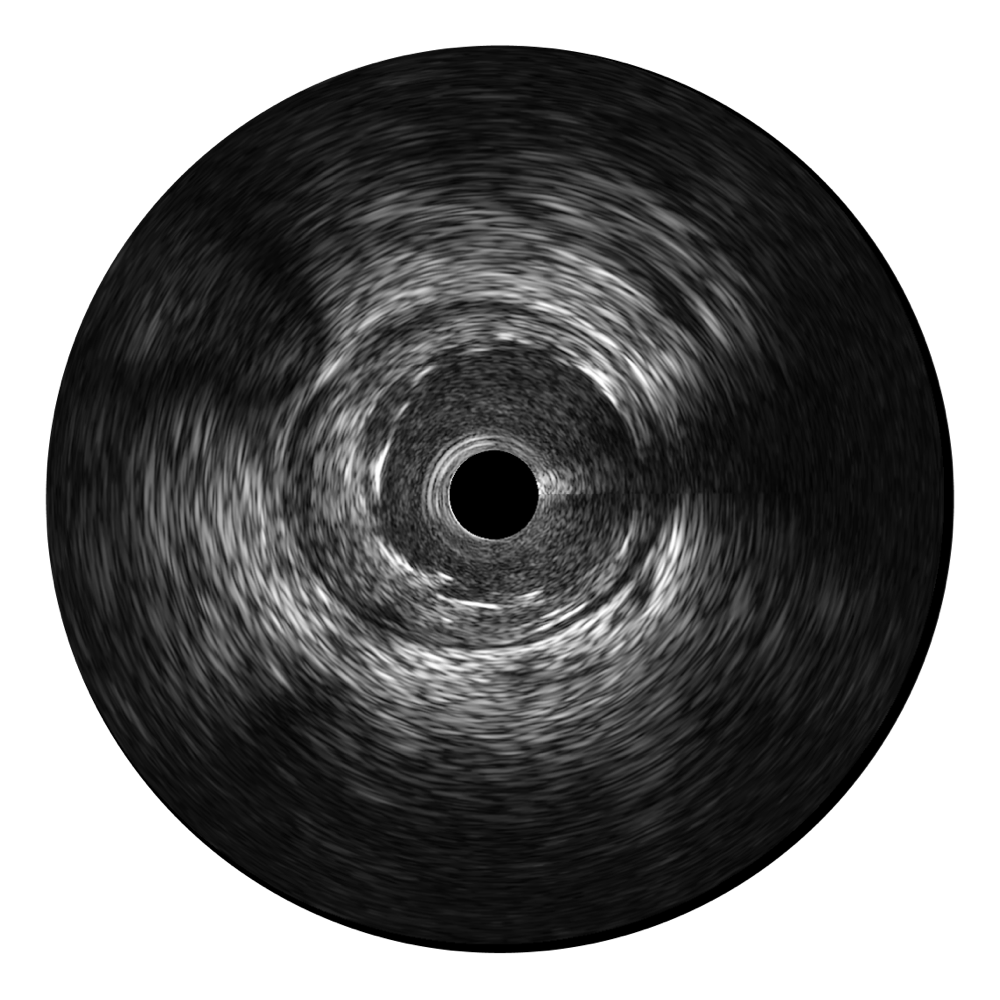

对比传统IVUS导管成像,百老汇电子游戏官网宽频IVUS图像的近场支架梁显影更细腻,远场中膜外血管仍清晰可辨,兼顾远中近,兼顾分辨力与穿透深度